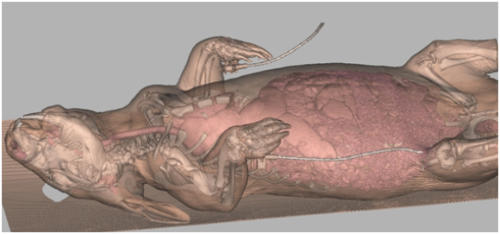

Do Hairy-nosed Wombats talk to each other? The University of Queensland in collaboration with the University of Vienna and Australian Animals Care and Education, have recently commenced a project to determine the importance of vocal communication in wombats. The project, which is supported by the Wombat Foundation, aims to investigate the behavioural ecology of the Southern Hairy-nosed wombat with the ultimate aim of relating these findings to the highly endangered Northern Hairy-nosed Wombat. The general objective of the project is to determine the biological information encoded by specific acoustic components of wombat vocalizations, and then use systematic playback experiments to investigate the functional roles of these acoustic cues in different social and reproductive contexts. Although we are in the early stages of the research, the results of the study appear to suggest that wombats have a characteristic vocal pattern that represents a signature for the individual animal, in much the same way that a human voice is distinctive. We have included a short wav file vocal recording of one of our female wombats know as Bella which was taken when she was protesting about being approached to be recorded. Parallel to these vocal observations has been an assessment of the vocal anatomy of the male and female using CAT scan technology at the University of Queensland Veterinary School, UQ Gatton. This amazing instrument takes multiple cross-section radiographs of the whole body of the wombat that can then be reassembled to produce a three dimensional image. You can see an image of our female wombat called Lolly, in which the CAT scan has revealed the skin, respiratory system, some of the digestive tract and the underlying skeleton